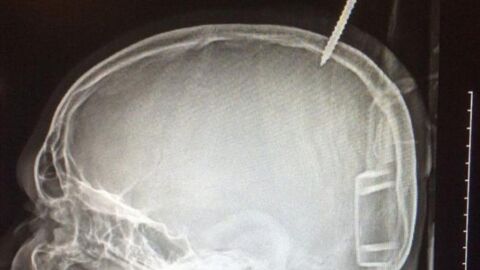

El mundo digital y las pantallas están modificando los comportamientos y capacidades de la mente humana. Con la neuropsicóloga Aroa Apraiz analizamos lo que está sucediendo y cómo solucionarlo.